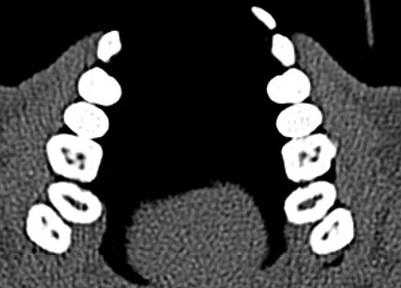

Ramamurthy и Matherene описывают ограниченность 2D изображений для определения MB2 каналов (Фото 1).

Фото 1: изображение MB2 в обоих первых молярах

Baratto Filho исследовали внутреннюю морфологию удаленных первых моляров верхней челюсти, сравнивая с данными, полученными при осмотре в микроскоп и при получении изображений КЛКТ ex vivo. Отчеты показали наличие 4-х каналов в 67,14% зубов и дополнительные корневые каналы в 92,85 % случаев в мезиобуккальном корне. Клиническая оценка показала слегка сниженный общий показатель (53,26%), но повышенный показатель выявления MB2 (95,63%), в то время как применение КЛКТ показало 37,05%. Ученые сделали вывод, что КЛКТ является хорошим методом для начальной оценки внутренней морфологии первого верхнего моляр, но для выявления устьев самым оптимальным способом является применение микроскопа. КЛКТ также применялся для выявления высокой встречаемости дистолингвального канала у Тайванцев, выявления аномалий в системе корневых каналов нижних премоляров, и помощи в выявлении искривлении корня (Фото 2).

Фото 2: Аксиальное изображение каналов C-формы во вторых молярах